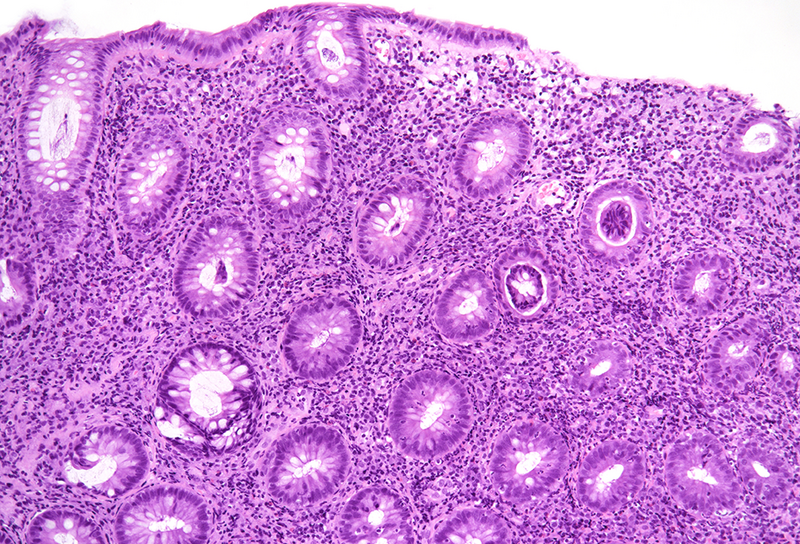

Rectum biopsies from a 35-year-old male with anal pain and haematochezia.

Chlamydia proctitis (Lymphogranuloma venereum).

Histological examination disclosed chronically inflamed large bowel mucosa with ulcer and fragments of granulation tissue (Panel A). In the preserved parts of the mucosa, there was mild crypt architectural distortion with occasional branching of crypts, but no prominent crypt irregularities or crypt atrophy (Panel B). The lamina propria contained a dense lymphoplasmacytic infiltrate which extended into the submucosa; few neutrophils and occasional active crypt inflammation / cryptitis were present (Panel C). Deep within the lamina propria an ill-defined non-necrotic granuloma was detected that consisted of a loose collection of epithelioid histiocytes (Panels D-E).

The histological findings were consistent with infectious proctitis, particularly with a sexually transmitted infection (STI). The deep and plasma cell-rich inflammatory infiltrate together with the occurrence of a granuloma indicated Lymphogranuloma Venereum (LGV) which is caused by infection with Chlamydia trachomatis serotypes L1, L2 and L3. Upon request by the clinicians, DNA was extracted from the FFPE biopsy samples and a real-time PCR assay was performed that confirmed presence of Chlamydia trachomatis specific DNA.

STI proctocolitis is underrecognized by clinicians and pathologists due to lacking awareness of the disease and its clinical and histological characteristics. It is often misdiagnosed as inflammatory bowel disease, but there are histopathological features that can help to distinguish STI proctocolitis from IBD. In contrast to IBD, STI proctocolitis is usually lacking prominent crypt architectural distortion, basal plasmacytosis and mucosal eosinophilia. In addition, crypt centered active inflammation (cryptitis, crypt abscesses) is much less pronounced compared to ulcerative proctocolitis and Crohn’s disease. By being familiar with the histopathogical pattern of STI proctocolitis, pathologists can contribute to timely and correct treatment and help to avoid patient mismanagement and STI transmission.